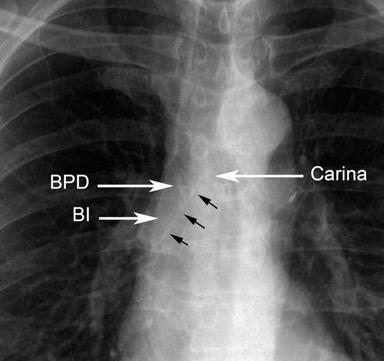

En el normal, el bronquio intermediario (BI) aparece en la proyección lateral, como una línea fina vertical que cruza el bronquio del LSI en su unión con el principal. (BPI) Engrosamiento del bronquio intermediario (BI)

97% de normales

Causas

Fallo cardiaco

Ca de pulmón

Metástasis

Linfoma

Sarcoidosis

Castleman

Schnur MJ et al.. Thickening of the Posterior Wall of the Bronchus Intermedius. Radiology. 1981

MJ et al.. Thickening of the Posterior Wall of the Bronchus Intermedius. Radiology. 1981 Ca. microcítico